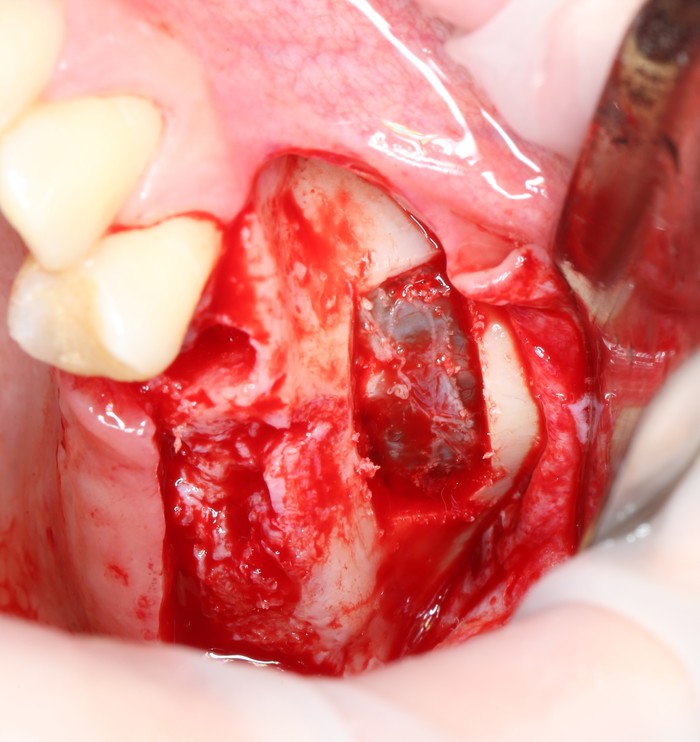

Разрез:

Скелетирование кости:

Мной и ортопедом было принято решение по удалению пятого зуба, потому как перелечить его будет, к сожалению, невозможно.

«Вжух»:

Лунка моментально заполняется кровяным сгустком.

Наконечником вырезается костная стенка и кладется в чашку с физ. раствором.

Хорошо видно слизистую оболочку, которая выстилает пазуху изнутри.

А это та самая костная стенка (толщина):